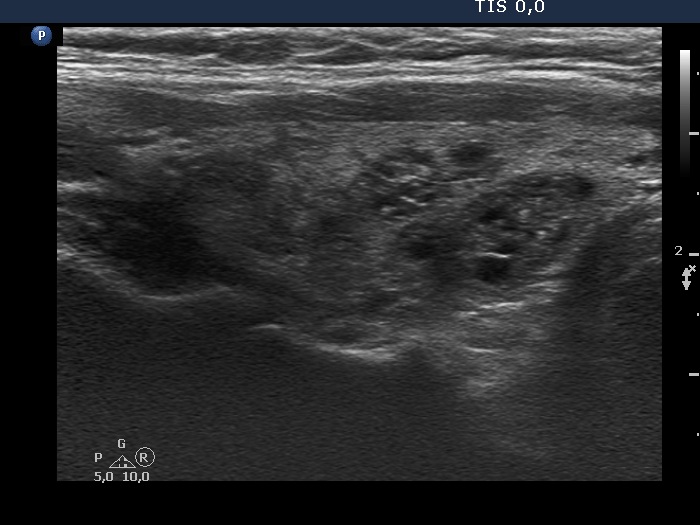

Discrete lesion or nodule in Hashimoto's thyroiditis - case 33 (1650) (ultrasonographic picture 4)

Right lobe, longitudinal view. The two cystic lesions having echogenic granules and lines are probably cystic nodules while the moderately hypoechogenic areas in the upper part of the lobe (left in the image) are presentations of thyroiditis.